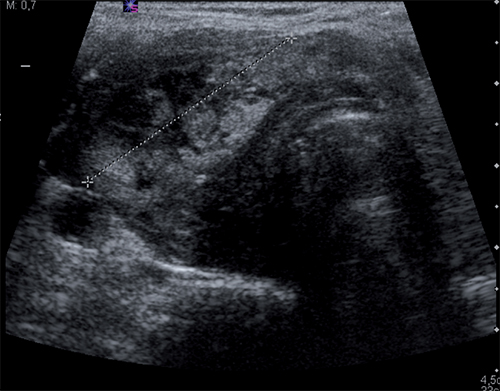

En la tomografía computarizada se apreciaba una tumoración heterogénea sobre el lóbulo tiroideo derecho que producía una desestructuración del mismo, provocando desviación de la tráquea hacia la izquierda, y comprimiendo el esófago. Se realizó punción aspiración con aguja fina (PAAF) guiada ecográficamente (Figura 1) del nódulo, obteniendo células con atipia de significado indeterminado, aunque insuficientes para indicar que la lesión fuese maligna.

Figura 1. TC cervical con masa infiltrante subglótica de que se extiende a tejidos extralaríngeos afectando a músculos infratiroideos derechos proximales, lóbulo tiroideo derecho y espacio prevertebral con pérdida de plano graso de separación con esófago proximal. No se visualizan adenopatías cervicales.